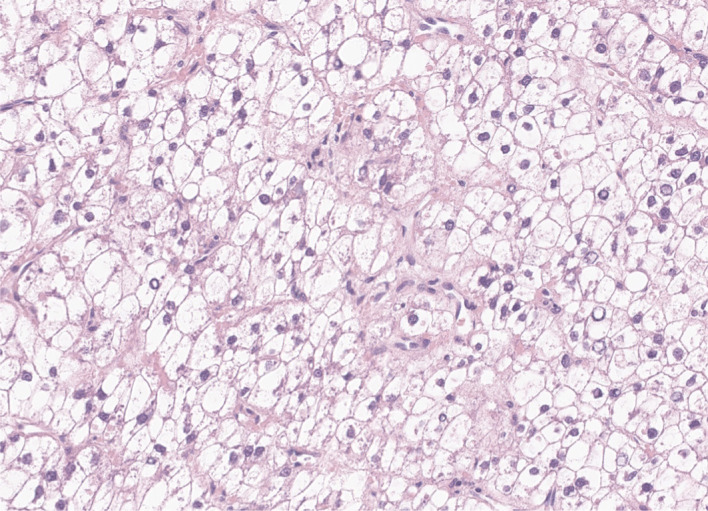

肝细胞癌(HCC)仍然是全球癌症相关死亡的主要原因,由于早期发现的挑战和目前治疗(如受体酪氨酸激酶抑制剂和免疫治疗)的疗效有限,临床结果不佳。HCC在组织病理学和分子水平上均表现出显著的异质性,这使其治疗复杂化,但为个性化治疗方法提供了潜力。本文概述了HCC的形态分子异质性,并总结了各种组织学亚型,包括脂肪肝型、透明细胞型、大梁块状型、硬化型、富含淋巴细胞型和纤维板层型HCC。每个亚型具有不同的临床、组织学和分子特征;例如,脂肪性肝细胞性HCC与代谢功能障碍相关,显示IL-6/JAK/STAT激活,而透明细胞型HCC通常有IDH1突变,预后良好。大小梁-块状亚型与预后不良和TP53突变有关,而硬化型hcc表达干细胞标记物并具有TSC1/TSC2突变。富淋巴细胞hcc的特点是免疫细胞浸润,预后较好。ctnnb1突变的hcc表现出特定的形态特征,可能受益于靶向治疗。了解这些亚型和相关的分子改变对于制定有效的诊断和治疗策略至关重要,包括潜在的预测性生物标志物和个性化治疗。此外,血管包膜-肿瘤簇等模式的识别提供了预后意义,并可能指导治疗决策。最近的分子研究增强了我们对HCC异质性的理解,为更个性化的治疗方法奠定了基础。病理学家在识别这些亚型,帮助预后预测和治疗计划方面发挥着至关重要的作用。数字病理学和人工智能的进步可能进一步促进生物标志物的研究,最终改善HCC治疗的患者结果。

Hepatocellular carcinoma (HCC) remains a leading cause of cancer-related deaths worldwide, with poor clinical outcomes due to challenges in early detection and limited efficacy of current treatments such as receptor tyrosine kinase inhibitors and immunotherapy. HCC exhibits significant heterogeneity at both histopathological and molecular levels, complicating its management but offering potential for personalized therapeutic approaches. This review outlines the morpho-molecular heterogeneity of HCC and summarizes various histological subtypes, including steatohepatitic, clear cell, macrotrabecular-massive, scirrhous, lymphocyte-rich, and fibrolamellar HCCs. Each subtype possesses distinct clinical, histological, and molecular features; for instance, steatohepatitic HCC is associated with metabolic dysfunction and shows IL-6/JAK/STAT activation, while clear cell HCCs often have IDH1 mutations and favorable prognosis. The macrotrabecular-massive subtype is linked to poor outcomes and TP53 mutations, whereas scirrhous HCCs express stemness markers and have TSC1/TSC2 mutations. Lymphocyte-rich HCCs are characterized by immune cell infiltration and better prognosis. CTNNB1-mutated HCCs show specific morphological features and may benefit from targeted therapies. Understanding these subtypes and associated molecular alterations is crucial for developing effective diagnostic and therapeutic strategies, including potential predictive biomarkers and personalized treatments. Additionally, the identification of patterns like vessels-encapsulating-tumor-clusters offers prognostic implications and may guide therapeutic decisions. Recent molecular studies have enhanced our comprehension of HCC heterogeneity, laying the groundwork for more personalized approaches. Pathologists play a vital role in recognizing these subtypes, aiding in prognosis prediction and treatment planning. Advances in digital pathology and artificial intelligence may further facilitate biomarker research, ultimately improving patient outcomes in HCC management.